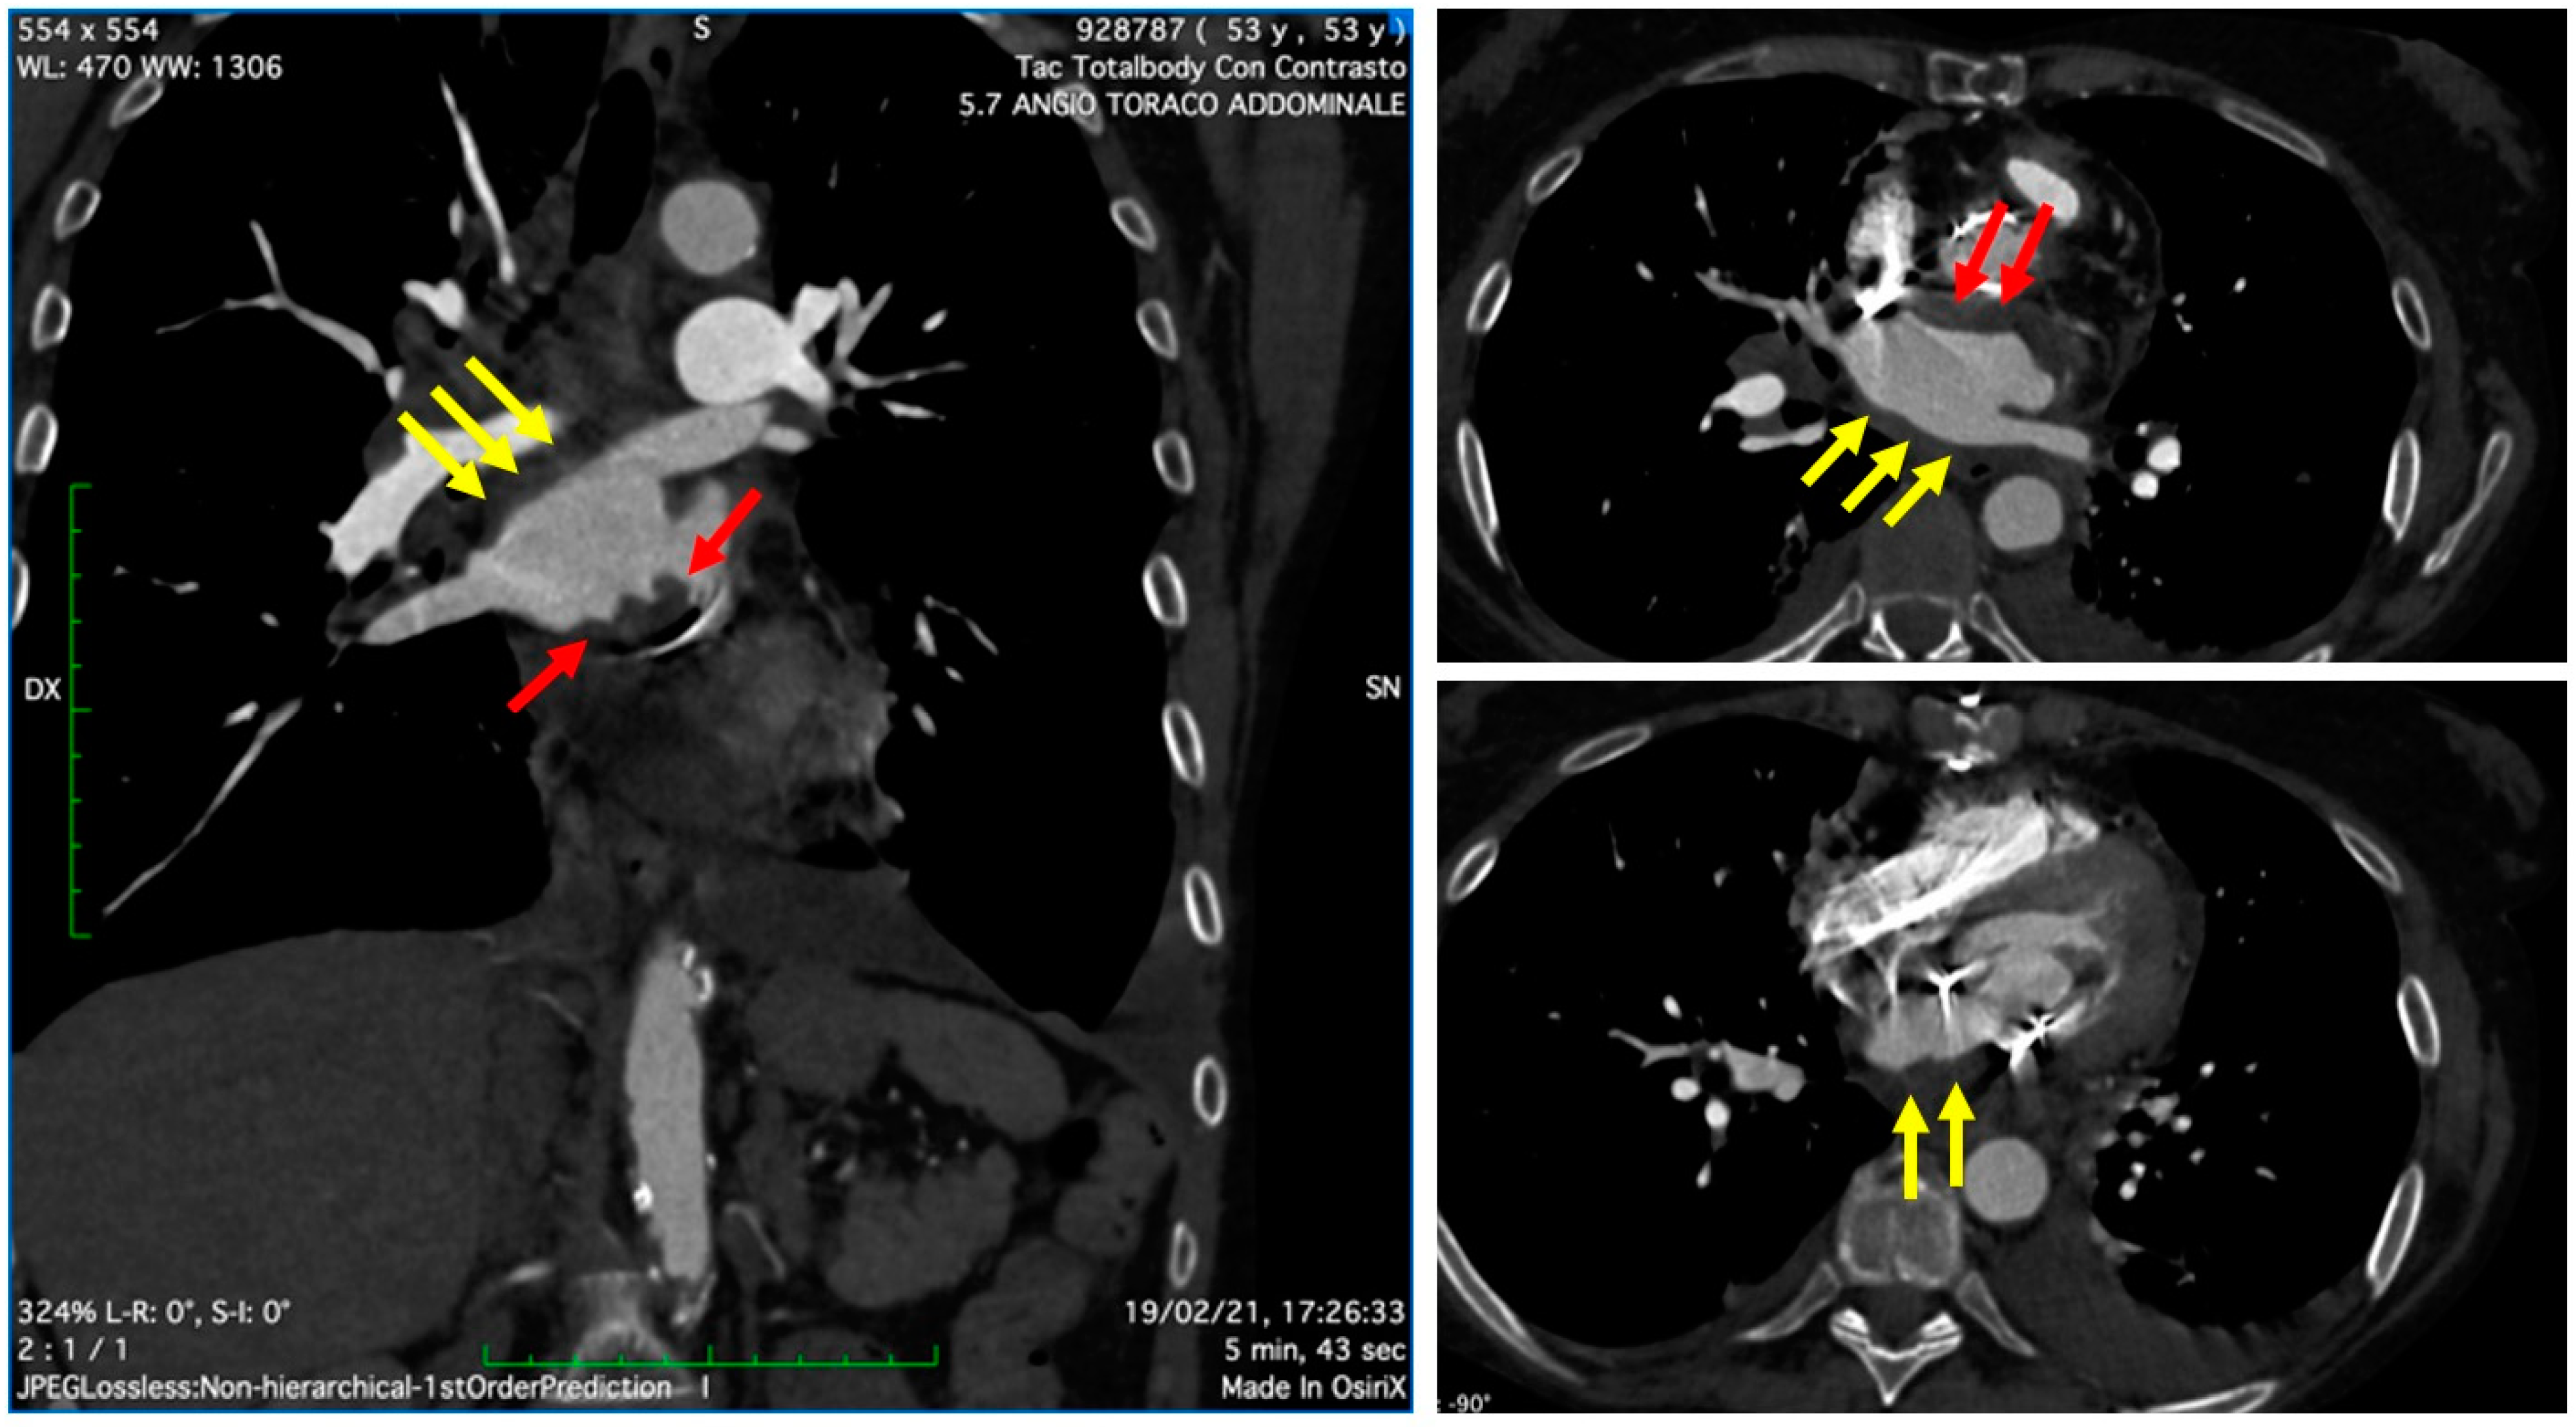

On 19 February 2021, the patient was referred to our center for a cardio-surgical assessment. At admission, the patient was in stable hemodynamic status andsymptomatic for dyspnea on minimal effort; however, she exhibited no orthopnea or resting dyspnea. The clinical assessment revealed the presence of diffuse ecchymosis, ischemia of the third toe of the right lower limb, and pulmonary basal rales; the EKG showed sinus tachycardia. Lab analysis showed an INR value of 3.5, normal renal function, increased white blood count with prevalence of neutrophils (14.280/μL, 82%), thrombocytopenia (50,000/μL), and 9-fold increase of D-Dimer (4.31 mg/L). A total-body CT scan excluded pulmonary embolism, revealed the presence of lung interstitial thickening and mild bilateral pleural effusion, and showed eccentric occlusive bilateral thrombosis of femoral veins, more prevalent on the right side; the cardiac phase showed extensive thrombotic stratifications in the left atrium (Figure 2). The TTE and TEE (Figure 3) showed mildly reduced systolic function (EF 50%) and gross and diffuse thrombosis of mitral prosthetic leaflets, prevalently on the ventricular side (thickness of approximately 1 cm), resulting in leaflet restriction and severe stenosis (mean gradient of 15 mmHg) with a severely reduced orifice area using 3D-guided planimetry (0.8 cm2). Moreover, a stratified thrombus (thickness of approximately 2 cm) was diffusely visible on the left atrial free wall. The aortic prosthesis had a mean gradient of 15 mmHg in the absence of thrombosis. The estimated systolic pulmonary artery pressure was 38 mmHg; an acceptable RV function (S’ 11 cm/s) was measured.

Figure 2. Cardiac CT showing extensive thrombotic stratifications in the left atrium, both on the posterior free wall (yellow arrows) as well as in the peri-annular region near the prosthesis ring (red arrows).